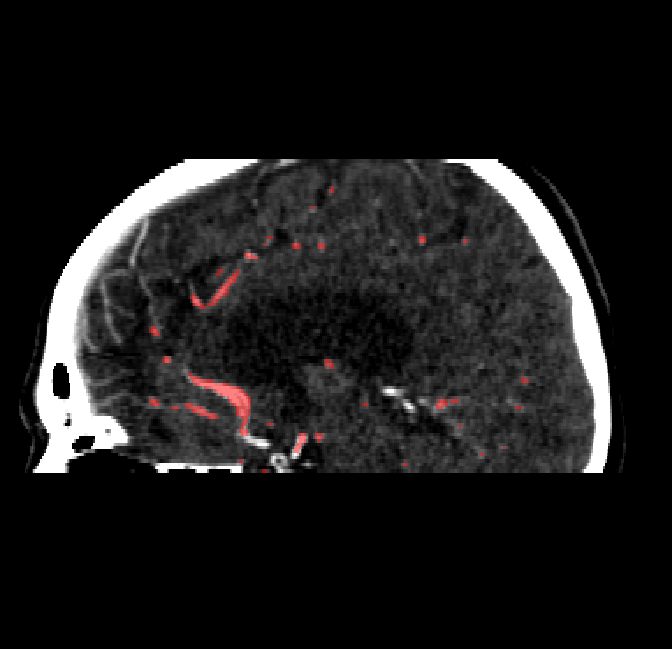

Qualitative Results

After fine-tuning, the two pre-train conditions appear to have little or no difference in terms of qualitative performance at the vessel segmentation task. However, when compared to the models trained only on real data, there are noticeable differences. Throughout Figures 4.3-4.9, the model pre-trained on scans with original CT noise is to be taken as representative of segmentation performed by the Perlin noise pre-training condition. Images showing the hand-labeled ground truth, as well as the unlabeled slice, are presented for comparison.

Figure 4.8: Side view of segmentations on regions near the left side of the skull. Unaltered image (left). No pretrain model (mid-left). Fine-tuned model (mid-right). Hand-labeled ground truth (right).

Figure 4.9: Side view of segmentations. Unaltered image (left). No pretrain model (mid-left). Fine-tuned model (mid-right). Hand-labeled ground truth (right).

The models appear to have a hard time segmenting vessels close to the skull surface. The model trained exclusively on patient data appears to struggle far more for these types on conditions than the fine-tuned models. Figure 4.8 shows an example of the fine-tuneds model having close to no trouble segmenting vessels near the left side of the skull, while the baseline model suffers heavily from false negatives. To lesser degree, this effect can also be observed in the frontal lobe of Figure 4.9 In the other hand, Figure 4.7 presents an example of both models failing to segment vessels near the top of the skull.

In the other hand, it should be noted that fine-tuned models suffered from false positives more often than models with no pre-training. The fine-tuned models appeared to occasionally segment regions near the skull, which although similar in intensity to vessels, had no resemblance in terms of shape. Examples of this are seen in Figure 4.4 near the occipital bone and near the right temporal bone. Examples of oversegmentation were observed to happen commonly around the internal carotid arteries. This is likely due to the amount of contact surface between the artery and the surrounding bone. There was also a tendency for all model conditions to segment bone regions that were similar in shape to large vessels (Figures 4.3 and 4.4). Bone structures in such regions have similar pixel intensities to the arteries transporting contrast material, which could explain the source of confusion for a model.